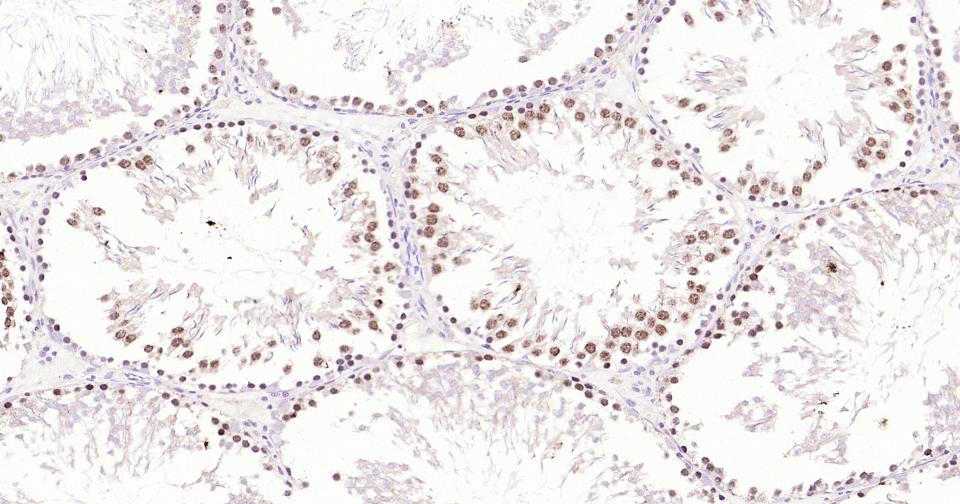

Paraformaldehyde-fixed, paraffin embedded Human Testicles; Antigen retrieval by boiling in sodium citrate buffer (pH6.0) for 15 min; Antibody incubation with TOP2A Monoclonal Antibody, Unconjugated(bsm-61077R) at 1:400 overnight at 4°C, followed by conjugation to the SP Kit (Rabbit, SP-0023) and DAB (C-0010) staining.